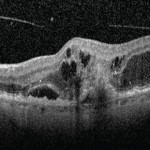

Diagnosi di RAP (retinal angiomatous proliferation): un approccio multi-imaging